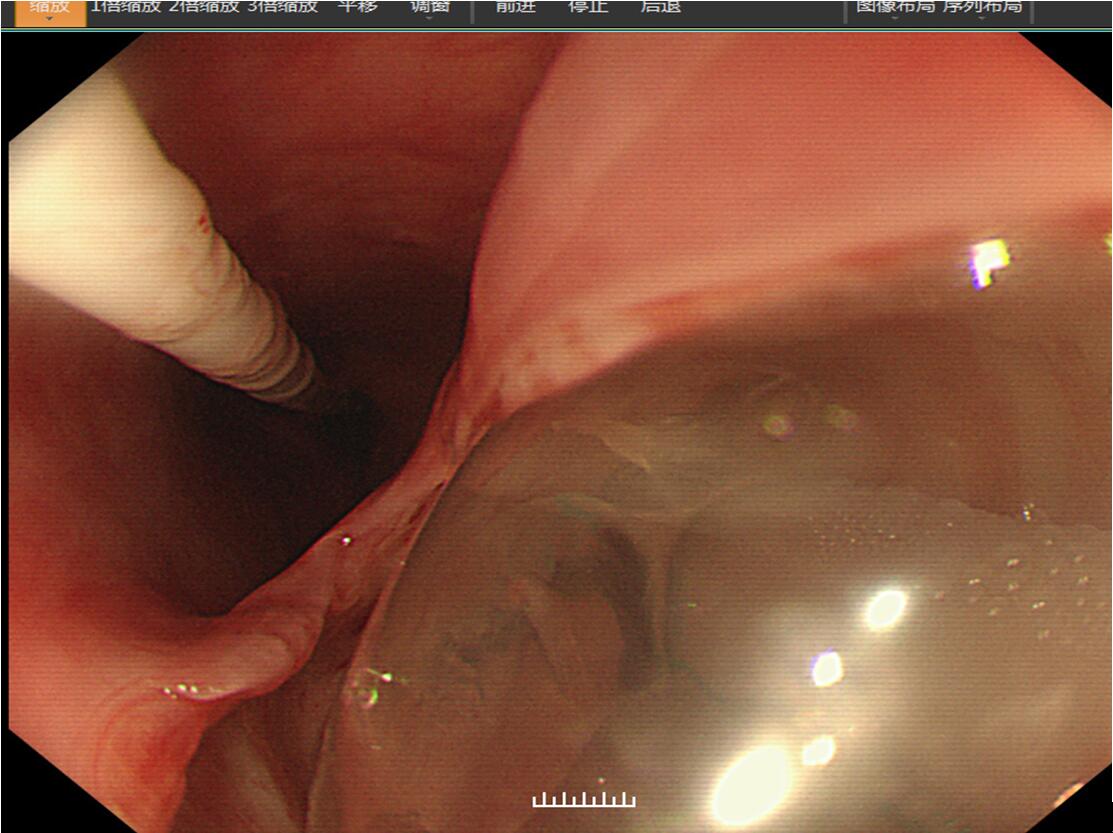

胃镜下清晰可见食管壁有一巨大的破口,气囊和气管插管“突破”重重阻碍到食管了。胸部CT和定位片都可明显看出来。

图1 12月26日胃镜检查时可见1.5cm*4.0cm的瘘口,气管插管清晰可见